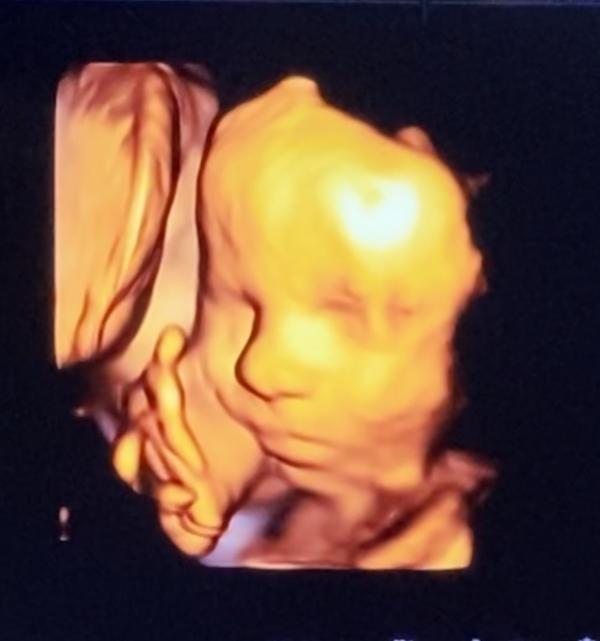

Привет 👋 #декрет #30недель 😁 Наконец-то мы добрались до УЗИ и увидели малышку 😍она такая забавная, все время улыбалась, потом закрылась ручкой и отвернулась 😁типа хватит 👌😉 Врач узи сказала- какая симпатичная малышка 🤗😍😉👌выходим на финишную прямую🙏🏼